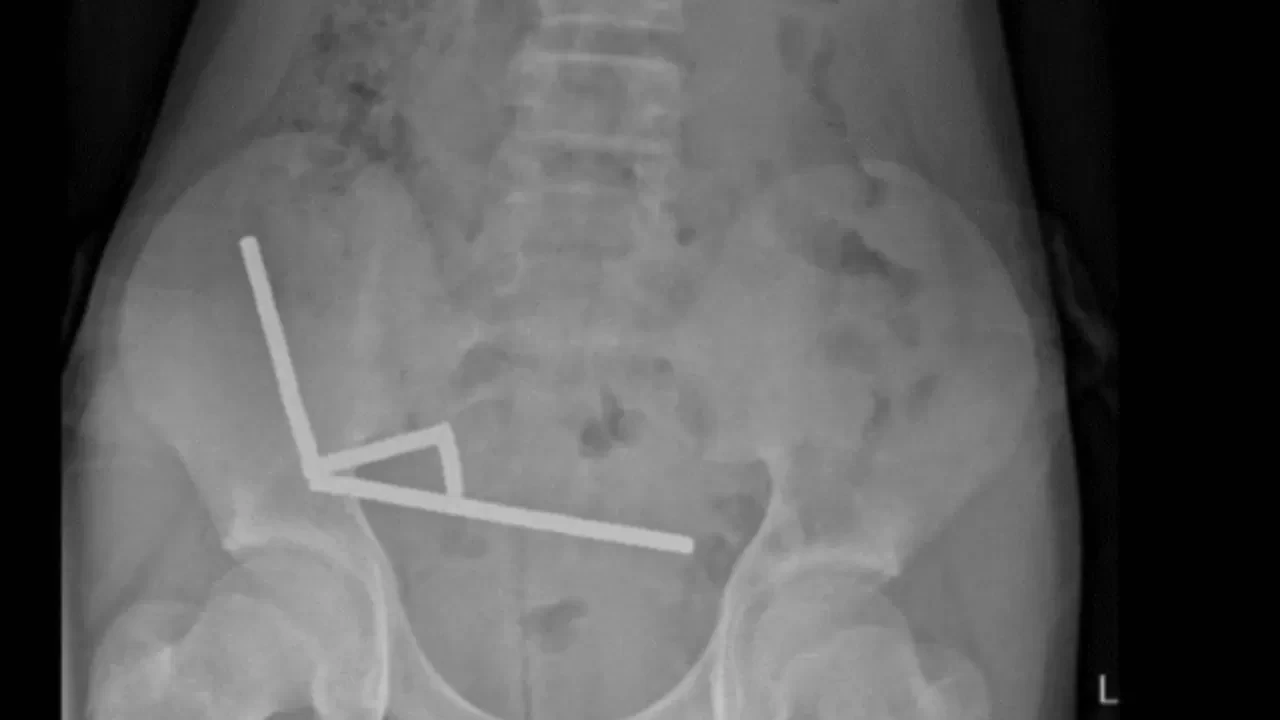

Röntgen görüntülerinde, çocuğun bağırsağında dört ayrı bölgede zincir halinde dizilmiş metal toplar görüldü. Ameliyatta bu zincirlerin ince bağırsak ve çekumda (kalın bağırsağın başlangıcı) birbirine yapışarak dokularda kan akışını engellediği ve “basınç nekrozu” denilen doku ölümüne yol açtığı tespit edildi.